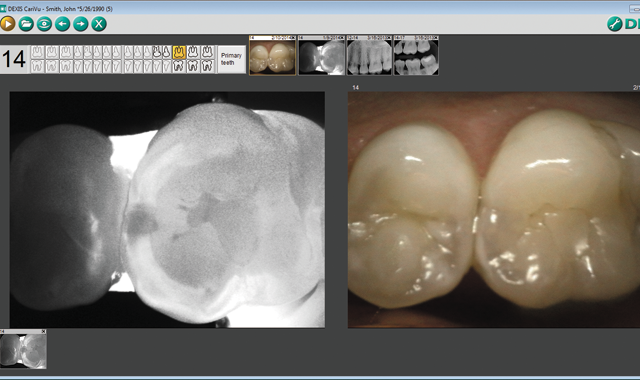

Additionally, we are very excited about the CariVu caries detection device. In conjunction with DEXIS digital radiographs and intraoral photographs, we can give our patients a complete picture of their dentition. Our youngest patients are already getting great benefits from CariVu. We start seeing children at three years old, and their mouths are either too small for radiographs, or they cannot sit still long enough for X-rays. Generally, we don’t start taking X-rays until the child is five or six years old. We have always felt that exams were not as thorough as we wanted without taking radiographs if the teeth had touching contacts. CariVu has helped us to fill this gap. With CariVu, we are finding proximal carious lesions that do not show up in X-rays -- often very large cavities. We can do our exams with confidence and ease as the children tolerate this with absolutely no discomfort. Their parents are equally thrilled because a majority of parents are against exposing their children to [ionizing] radiation, especially at these early ages.

CariVu shines in both diagnostics and presentation. Every operatory in my office has two viewers, one screen behind the patient for me and one on the wall for the patient to see. Patients love the fact that without any radiation, we can give them this level of visually explanatory diagnostics. A CariVu picture is worth a thousand words.

With CariVu, the fact that we can often detect caries that may not otherwise be found on an X-ray really creates that “wow factor” with the patients. When they can visually see caries on the CariVu image, it makes them want to take action to fix the problem. I can see tooth fractures, and actually show the patient the fracture that is the reason for my suggesting a crown. The image is very explanatory. With an intraoral camera image, many times I am pointing at lines I am not sure that they can see -- but with the CariVu, they can see the fracture or the cracks in the teeth. And even better, we are achieving all of this without radiation. If the average patient today sees technology working in a positive manner, they get excited about it.

CariVu is a great adjunct to digital imaging. On kids where I cannot get a bitewing because of the cooperation of the child, the CariVu is an easier device to use, and I can find decay. Even if we were unable to obtain an X-ray, I can still properly treat and diagnose caries or know to watch the area.

film X-ray and trying to point out certain small areas of concern, unless the image is very big, most parents won’t see or understand what I am talking about. With CariVu, if I am taking an occlusal view picture, it is much easier to see a dark or black spot on a picture that I can blow up larger. With digital X-ray, I can use digital tools within the DEXIS software -- I can either invert the image, or use a highlighting circle where I am actually able to enhance the image and make a clearer image with the highlight over the cavity or the decay I am trying to show the parent.

More on CariVu™

DEXIS CariVu™ is a compact, portable caries detection device that uses patented transillumination technology to support the identification of occlusal, interproximal and recurrent carious lesions and cracks. By hugging the tooth and bathing it in safe, near-infrared light, CariVu makes enamel appear transparent while porous lesions trap and absorb light. This allows the clinician to see through the tooth exposing its structure and the actual structure of any carious lesions with very high accuracy.